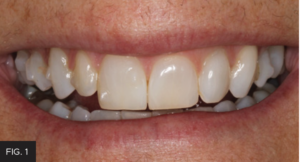

After the patient’s crowding issues had been corrected with orthodontics, the gingival display at #7 was excellent. All that remained was to restore the tooth to proper dimensions. (FIG 3 & 4) Different treatment options were discussed with the patient, including a composite veneer, Class IV restoration, and minimal-preparation porcelain veneer. Each option’s expected longevity was explained. The patient chose to have the tooth restored with a Class IV mesial-incisal-distal restoration.

The pre-operative right 1:1 view shows deep incisal embrasures on tooth #7 and orthodontic composite tabs.

The post-operative right 1:1 view shows how all the characterizations make such a life-like restoration that blends the restoration into the tooth and the dental arch.